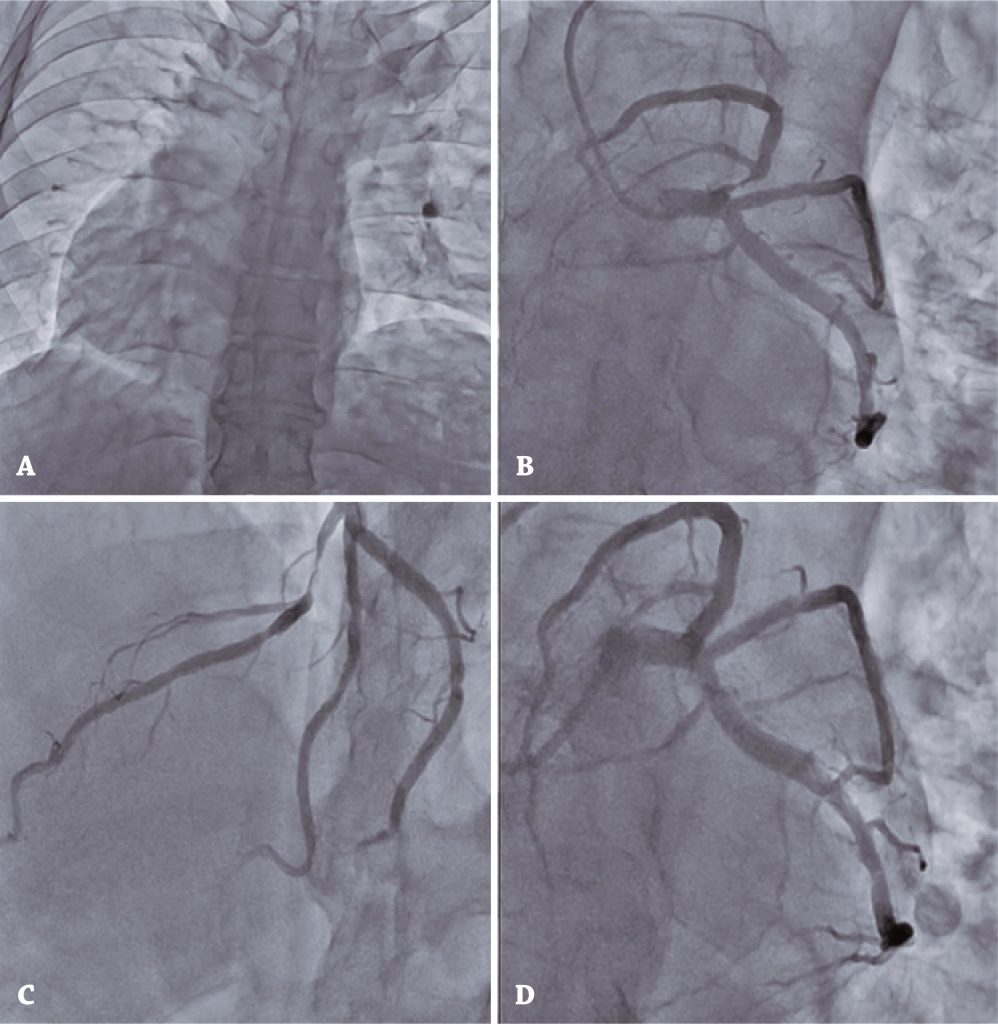

Figura 2

Cinecoronariografia e intervenção coronária percutânea. (A) Dextroposição. (B/C) Grave lesão proximal da descendente anterior. (D) Resultado da intervenção coronária percutânea com implante de stents.